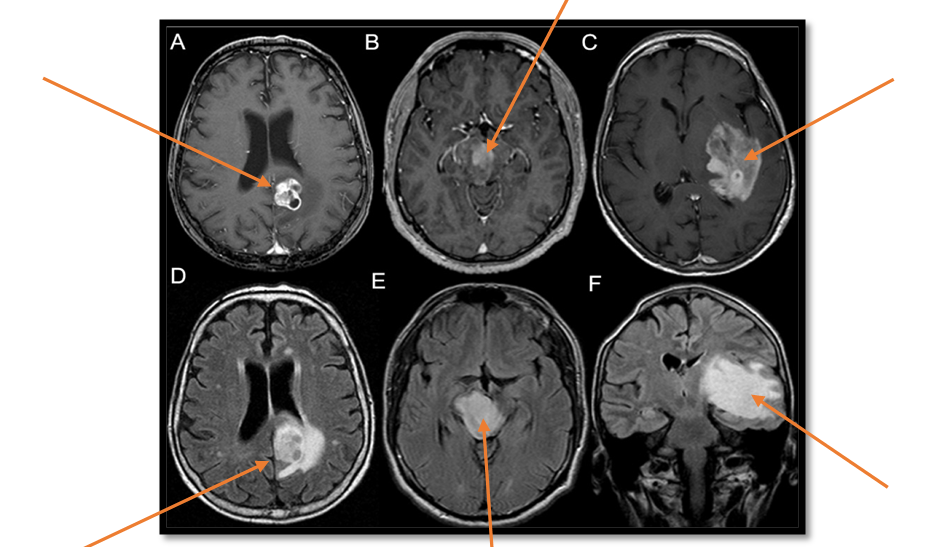

- МРТ головного мозга (в 3-х проекциях в стандартных режимах (Т1, Т2, FLAIR, Т1 + контраст) – золотой стандарт в диагностике опухолей головного мозга;